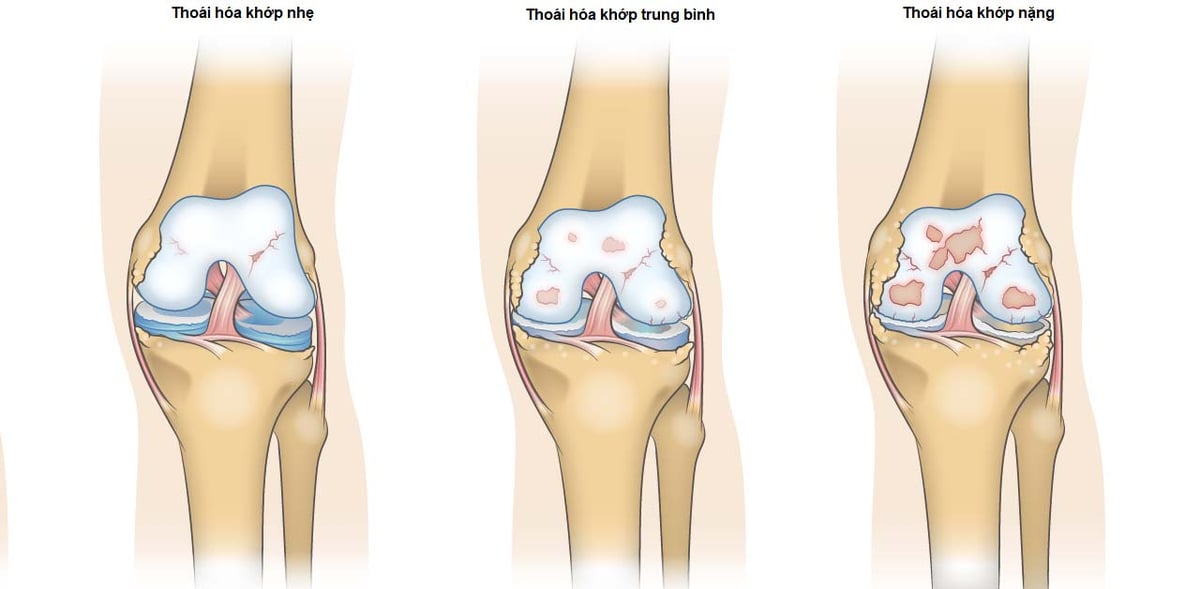

Bệnh viêm khớp gối tràn dịch gây đau khi bệnh nhân đi lại

Bệnh viêm khớp gối tràn dịch là tình trạng lượng dịch trong khớp gối nhiều lên, có thể phát hiện dễ dàng trên lâm sàng. Bệnh viêm khớp gối tràn dịch làm hạn chế cử động của khớp gối và có thể gây đau khi bệnh nhân đi lại. Theo các bác sĩ, tình trạng […]